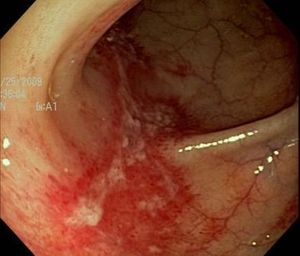

These endoscopic findings help explain worsening dysphagia in a 32-year-old man. Esophageal biopsies prove positive for eosinophilia. How would you proceed?